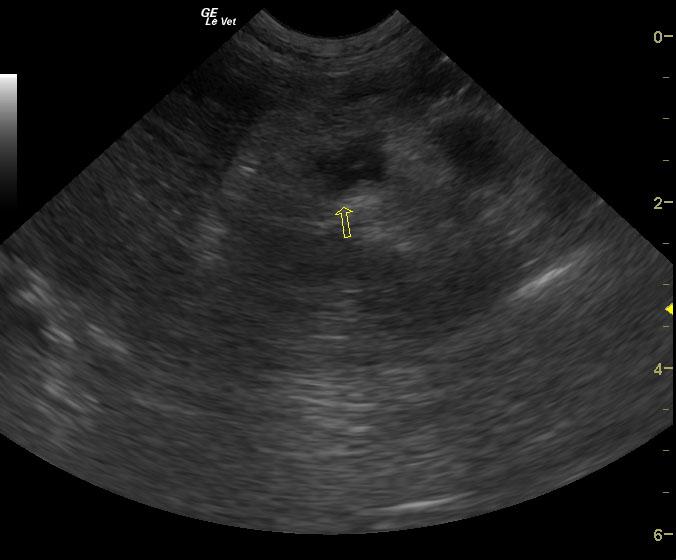

Extensive mixed hypoechoic pancreatic parenchyma is noted much of which lacks blood flow on power Doppler assessment. Gastroduodenal thickening is noted with duodenal spasm. Cavitations are noted in the pancreas with echogenic fluid. Extensive hyperechoic fat is noted.